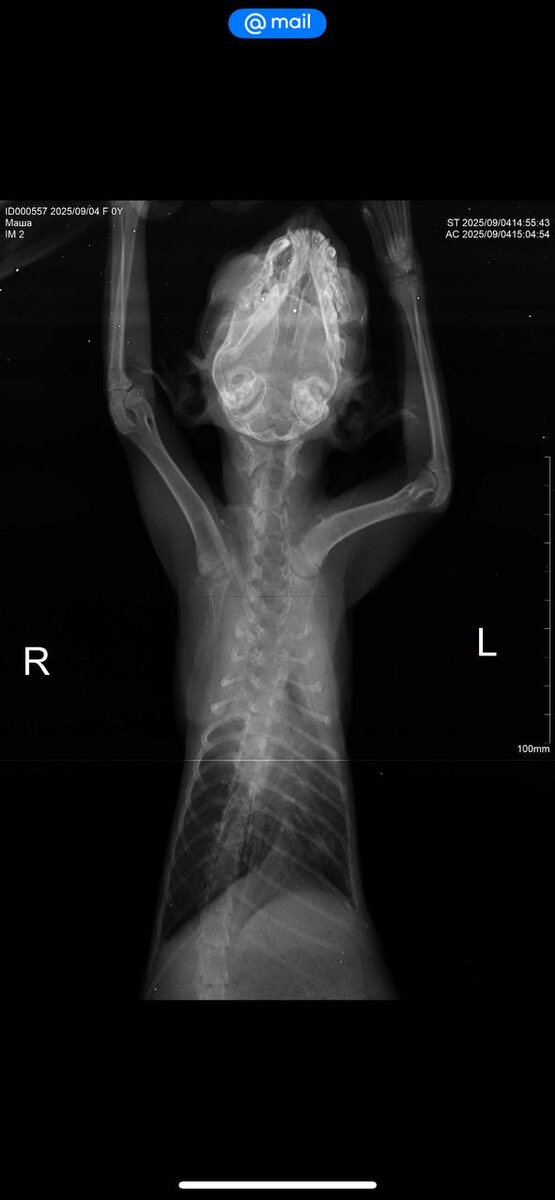

Друзья доброе утро! Новости по новой малышке 🙏🏻. Я ее назвала Машенька . Вчера сделали рентген . По нему начальная стадия отека легких и предположительно диафрагмальная грыжа около сердца . Диагноз пока предположительный . Мы продолжаем лечение и сидим в кислородном боксе . Через неделю надо будет переделать рентген.

Вчера сделали рентген . По нему начальная стадия отека легких и предположительно диафрагмальная грыжа около сердца . Диагноз пока предположительный . Мы продолжаем лечение и сидим в кислородном боксе . Через неделю надо будет переделать рентген.